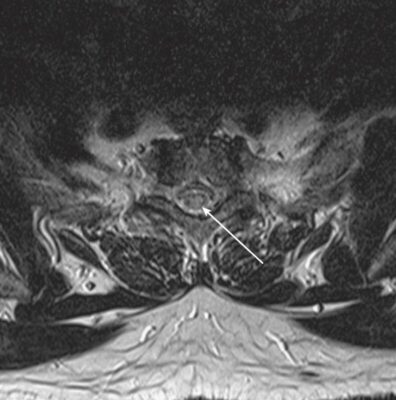

- Thăm dò tốt nhất khi nghi ngờ viêm tuỷ cắt ngang là MRI. MRI không chỉ cho phép nhìn thấy tổn thương mà còn loại trừ các nguyên nhân có thể điều trị được, chẳng hạn như khối u, áp xe và các tổn thương khác gây ra bệnh lý tủy do chèn ép. Chất cản quang có thể được dùng để làm nổi bật các tổn thương, và chụp tủy hiếm khi được xem xét nếu không có MRI.

- Theo một nghiên cứu chụp cộng hưởng từ (MRI), viêm tuỷ cắt ngang cấp tính vô căn thường ảnh hưởng nhất đến vùng tuỷ cổ (60%), tiếp theo là vùng tuỷ ngực (33%).

- MRI cho thấy các đặc điểm giúp phân biệt viêm tuỷ cắt ngang với các bệnh lý như bệnh xơ cứng rải rác.

- Tổn thương ở viêm tuỷ cắt ngang có xu hướng ảnh hưởng đến vùng trung tâm của tủy và liên quan đến hơn 2/3 đường kính của tủy, trong khi ở bệnh xơ cứng rải rác, tổn thương thường ở ngoại vi hơn và liên quan đến ít hơn một nửa đường kính của tủy. viêm tuỷ cắt ngang thường có cường độ tín hiệu cao trên hình ảnh T2W kéo dài theo chiều dọc trên nhiều khoanh tuỷ sống hơn. Số lượng các khoanh đoạn tuỷ bị ảnh hưởng có thể từ 1 hoặc 2 đến 11, và đôi khi ảnh hưởng đến hành tuỷ.

- MRI não có tăng cường tương phản thường được thực hiện để giúp xác định xem các dấu hiệu trên MRI có hướng đến bệnh xơ cứng rải rác chứ không phải viêm tuỷ cắt ngang “vô căn” hay không.

- Trong viêm tuỷ cắt ngang một phần vô căn, một kết quả không cho thấy tổn thương não có nghĩa là khả năng tiến triển bệnh xơ cứng rải rác ở mức 15% đến 44%. Khi thấy các tổn thương não như mảng chất trắng (đặc biệt là quanh não thất), nguy cơ phát triển bệnh xơ cứng rải rác tăng lên từ 44% đến 93%.